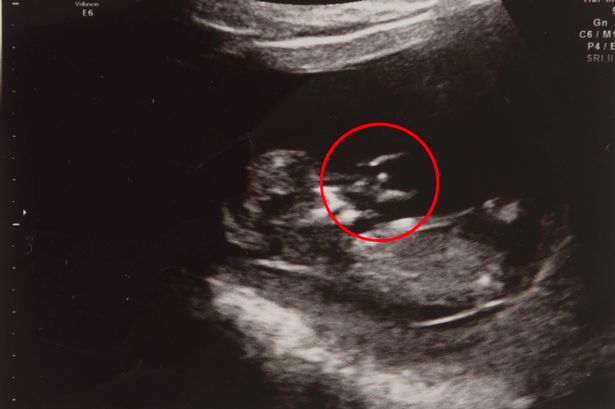

Nhìn thấy thiên thần trong hình ảnh siêu âm, Jennifer tin chắc con của mình sẽ được thiên thần bảo vệ. |

Thai phụ Jennifer 29 tuổi phải tiến hành phẫu thuật sau khi bị chấn thương và sinh mổ vì thai nhi đã quá 14 ngày dự sinh. Cô tin rằng đốm nhỏ xuất hiện trong bức hình siêu âm thai nhi chính là thiên thần bảo vệ cho đứa con của mình và chắc chắn con trai sẽ được cứu sống.

Tuy nhiên dù lo lắng nhưng cô tin con trai mình sẽ vượt qua được vì đã có thiên thần phù hộ. Cô cho biết cô đã nhìn thấy thiên thần trong hình ảnh siêu âm khi bé Joseph 16 tuần tuổi.

Jennifer chia sẻ rằng: “ban đầu tôi không biết đó là hình ảnh của một thiên thần, tôi đã lo sợ các bác sĩ sẽ nói với tôi rằng có chuyện gì đó sảy ra với con tôi. Nhưng mẹ tôi nhận ra đó là hình ảnh một thiên thần, thật sự kinh ngạc. Tôi cũng đoán đó thật sự là thiên thần, một thiên thần đã bảo vệ con tôi sau bao nhiêu chuyện khó khăn xảy ra.”